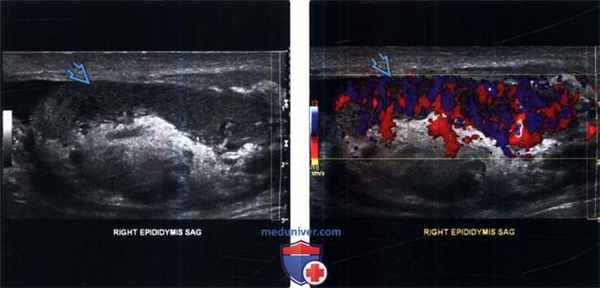

(Слева) УЗИ правой мошонки в сагиттальной плоскости, В-режим: утолщенный гетерогенный и гипоэхогенный придаток.

(Справа) Цветовая допплерография придатка: у этого же пациента выявлена заметная гиперемия придатка, что характерно для острого эпидидимита. В сомнительных случаях целесообразно сравнивать данные допплерографии и В-режима.